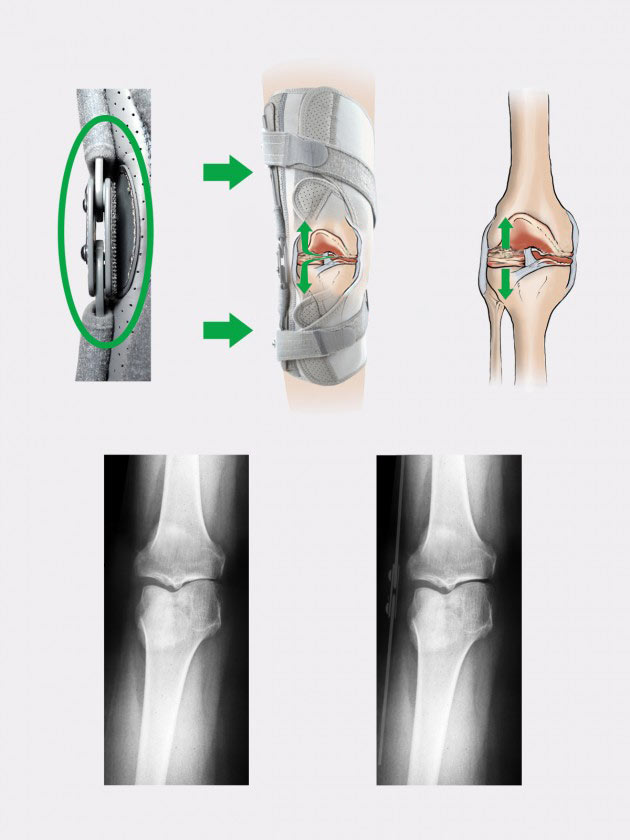

The ideal solution to prevent OA is single upright brace ATTACK 2RA.

The external parts of the splint are equipped with rotating buckles where two dynamic force straps go. The straps allows to separate two knee joint surfaces what reliefs the pain and prevents against the OA progress.

Double axis splint 2RP is the orthopaedic splint that reflects anatomic knee movement while flexion. The drop locks do not change their position relative to the axis of a knee joint. 2RP splints are reinforced polycentric splints, equipped with an articulated mechanism, the main element of which are sliders moving on parabolic tracks. These type of splints is primarily used in knee braces, where strong lateral stabilization of the knee joint and precise regulation of its mobility are essential. The arms of the splint are made of high-quality aluminum alloy, hot-coated with a durable powder coating, what makes them very light. Moreover, their surface is resistant to patient’s sweat and salt contained in it. The drop locks are made of very durable and strong acid-resistant steel in which a special hole system with threads were made. The splints are waterproof and can be used in wet and humid environments.

The splint is equipped with the hyperextension knee lock and has following angles of joint flexion: free joint, 10, 30 ,40, 60, 75, 90 degrees and the following angles of joint extension: 10, 20, 30, 40 degrees. The ROM adjustment is made with a special, hardened screws placed into threaded holes marked with a specific angle value we want to lock. In this kind of splint, you can lock not only the angles of flexion and extension of a knee joint, but also the desired range of knee joint movement. Each brace equipped with 2RP splint comes with a free Allen key for these settings. This method of adjusting drop locks in orthopedic splints prevents from their setting by unauthorized persons who do not have a key. The bottom part of the drop lock has an oval shape that allows you to attach a soft anatomic pad made in 3D technology that separates drop lock from the knee. All movable elements of the splints move on galvanized steel rivets and in order to prevent them from seizing, special Teflon sliders were used in these places. Such a construction ensures their maintenance-free operation.